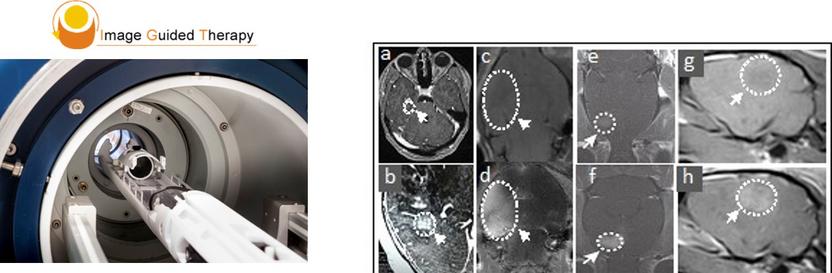

MRgFUS BBBD in tumor-bearing rodents, canines, and humans. T1-weighted post contrast images before and after MRgFUS in non-enhancing brain tumor regions, respectively: (a, b) human, (c,d) mouse, (e,f) rat, and (g,h) canine.